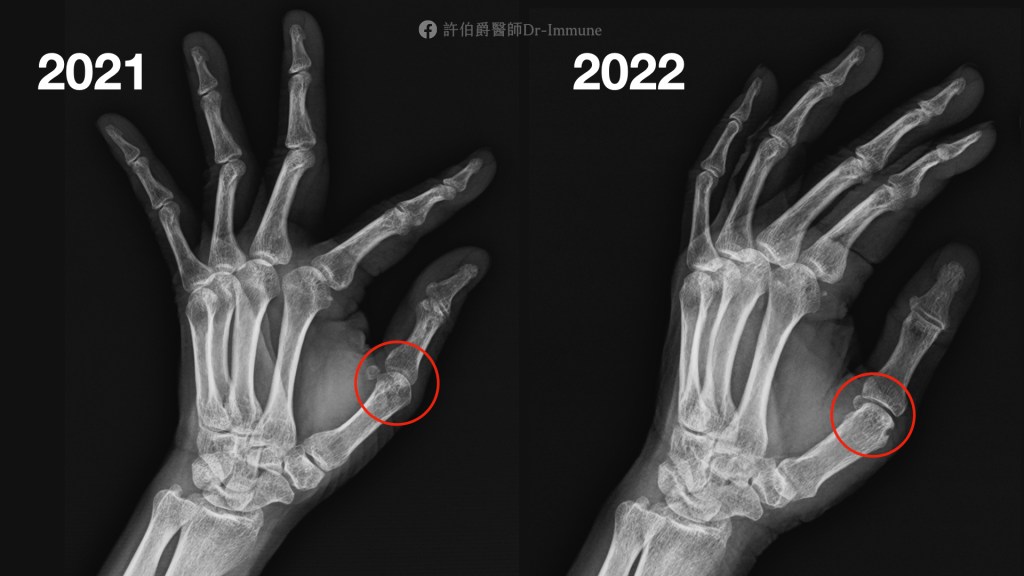

然而就在每年的X光追蹤的時候,看出她的關節已經有侵蝕病變的問題。

拿2022年的X光與2021年相比,特別是在左手拇指的掌指關節出現新的黑孔,那是關節被吃掉的痕跡。右手的手肘也因為關節侵蝕變得關節面較為狹窄與模糊。

許醫師在身體檢查上也可以摸得出D小姐的右手肘與左手拇指的掌指關節都有腫脹的情況,她也感覺到左手拇指的掌指關節有壓痛感,儘管她平常都只關注那個打不直的右手肘。